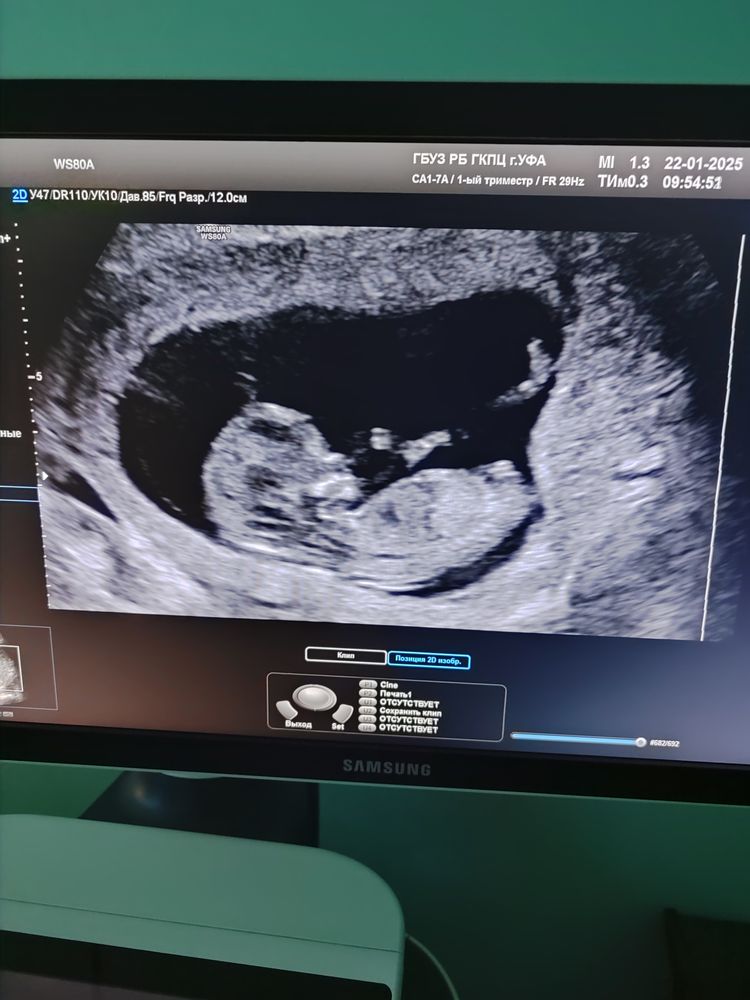

жду девочку, 16 неделя Уфа

Пол по фото

Предположительно девочка, у мальчиков бугорок на верх. Но там не особо понятно, так что лучше подождать, мне на первом скрининге сказал узист предположение и не ошибся)))

Kamila E, бугорок на фото даже вниз чуть, что позволило девочку предположить

А есть другое фото? По этому фото девочка будто.

К сожалению по УЗИ непонятно